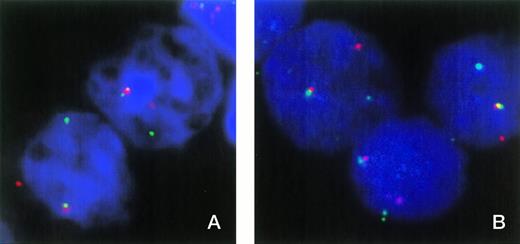

FISH was used to show the involvement of ETV6 in patient no. 1. In normal nuclei, FISH with cosmids for ETV6 exons 1 and 8 shows two fusion signals indicating two intact ETV6 genes. Patient material showed one fusion signal and single, separate red and green signals, indicating a breakpoint in one ETV6 allele and that the normal allele is not grossly deleted (Fig 1A). However, this result does not exclude the possibility of a small intragenic deletion or other mutation that may have inactivated the normal copy of ETV6.

(A) FISH analysis of two nuclei from patient no. 1 with cosmids 179A6 (detected with rhodamine) and 148B6 (detected with FITC), which hybridize to ETV6 exons 1 and 8, respectively. Colocalized signals indicate the normal ETV6 allele, while separate red and green signals indicate a break within ETV6. (B) Three nuclei from patient no. 1 hybridized with cosmids 179A6 (detected with rhodamine) and ICRFc108G2043QD2 (CDX2 exon 1 plus upstream sequence, detected with FITC). Colocalization of these cosmids indicates a chromosome 13 break upstream of CDX2 exon 1.

The fact that the 3′ RACE PCR product and the larger ETV6-CDX2 fusion transcript contained a sequence that matched a region shortly upstream of the mouse Cdx2 gene strongly suggested that the chromosome 13 breakpoint must lie upstream of the human CDX2 gene. This hypothesis is supported by the fact that no reciprocal CDX2-ETV6 transcripts were detected. To confirm the position of the breakpoint, two chromosome 13 cosmids containing the region immediately upstream of human CDX2 were isolated by screening a library with the inserted sequence from the larger fusion transcript. PCR analysis showed that clone ICRFc108G2043QD2 also contained CDX2 exon 1 and that clone ICRFc108B0629QD2 contained upstream sequence only. Both cosmids hybridized to chromosome 13q12 only in normal control metaphases. Two-color FISH analysis on nuclei from patient no. 1 showed colocalization of both these cosmids with the ETV6 exon 1 cosmid (Fig1B), thus confirming that the break is upstream of CDX2 exon 1.